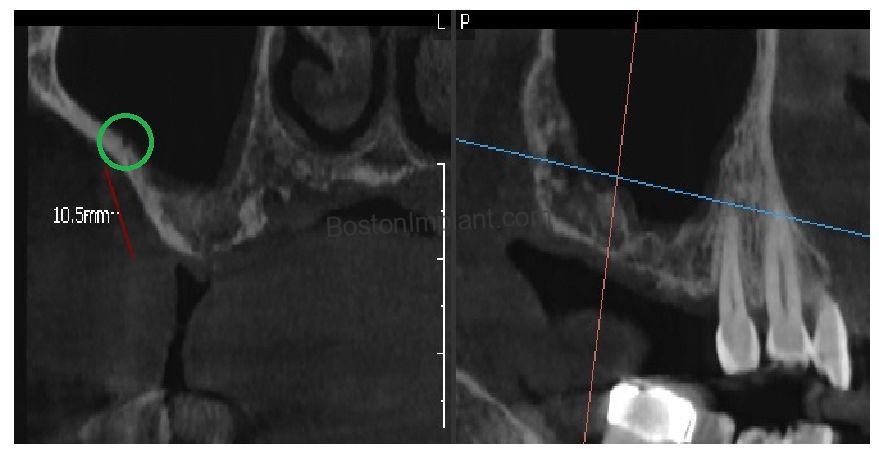

Clinical Insight: In the surgical planning image above, you can see that more than half of the projected implant length would have sat in the empty space (dark area) of the sinus cavity rather than in solid bone (white area). So, we planned sinus graft on upper right side. For more information about sinus graft, check out this post below

2. Navigating Anatomy: The Blood Vessel Using our 3D CBCT scan, we identified a small blood vessel (Green circle below) crossing directly through the intended surgical access site. Damaging this vessel can cause complications, so we used our high-resolution imaging to map a precise entry point that bypassed the vessel entirely.